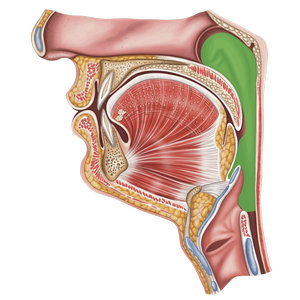

Epiglottis

Piece of cartilage in the throat that protects the airway during swallowing (in green)